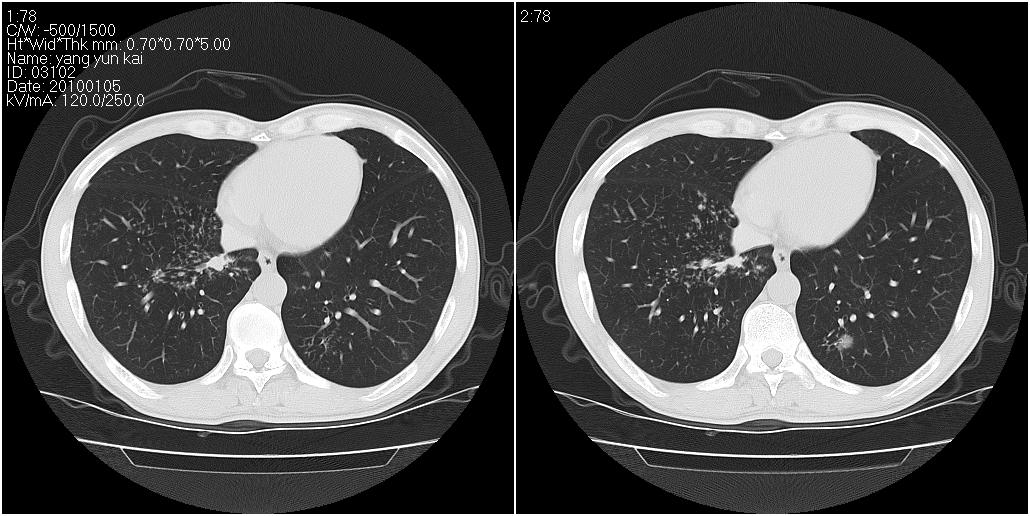

标题: CT23980:男性,47岁。近来咳痰、咳血,血沉增快(40左右),

男性,47岁。近来咳痰、咳血,血沉增快(40左右),痰中未检出结核杆菌。

两肺继发性肺结核并多发性结核球形成,部分病灶内空洞形成。